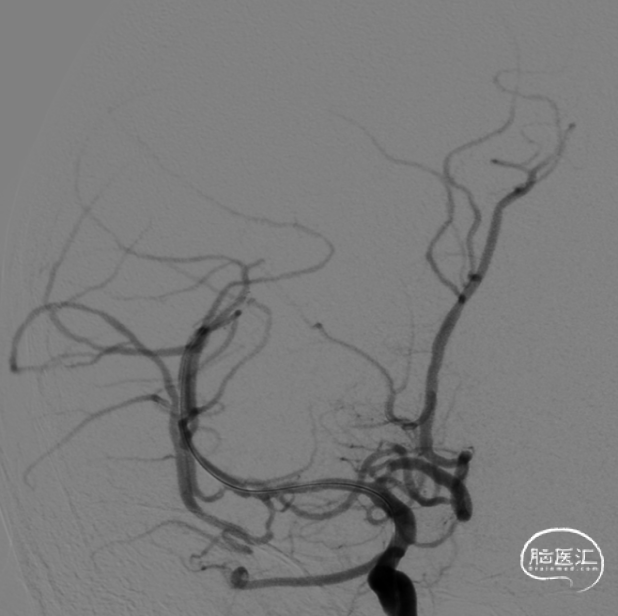

MRA示:右侧大脑中动脉闭塞

术前右侧颈内动脉造影示右侧副大脑中动脉